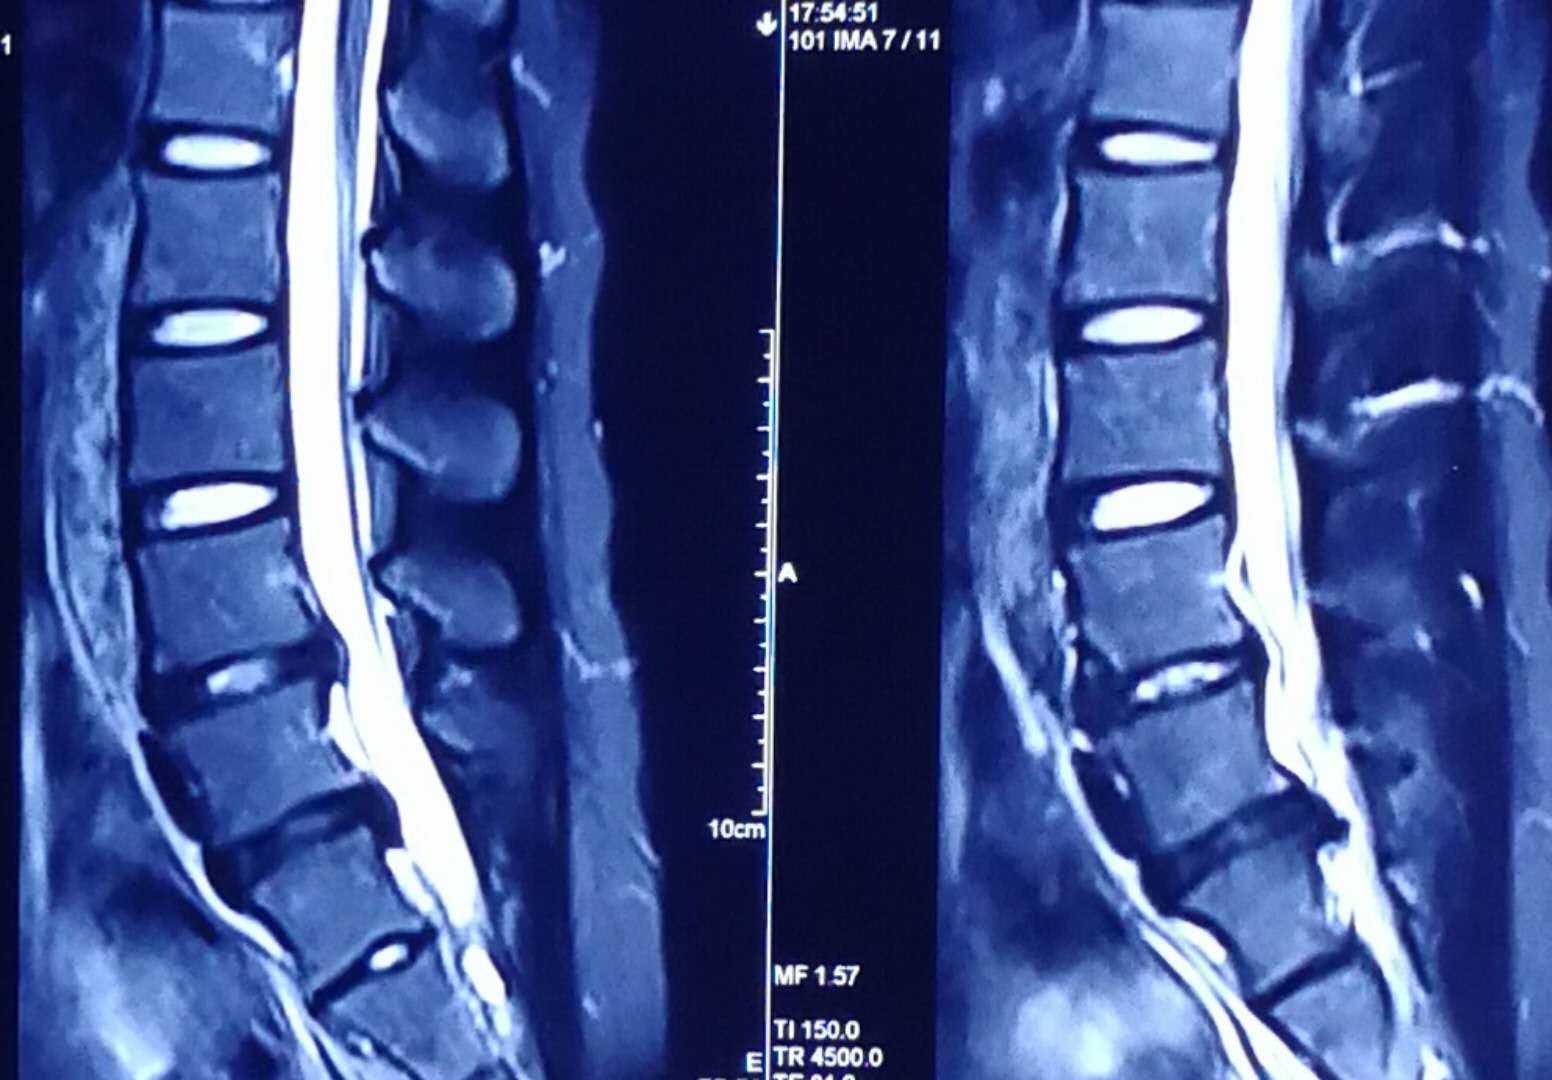

从磁共振片子上看,突出间隙位于腰4、5和腰5骶1,以腰5骶1间隙的椎间盘突出尤为明显,属于左后方的巨大突出,腰5神经根明显被挤压,已经看不清神经的走向,但右侧的神经根影子十分清楚,出现患肢的麻木也就是理所当然的了。目前体检发现左下肢直腿抬高试验40度阳性,加强试验阳性,右侧均为阴性,左侧小腿后外侧及足背外侧也有片状皮肤感觉减退区域,左侧跟腱反射微微有些减弱,右侧是正常的,看得出,骶1神经根是受到了一定的伤害。